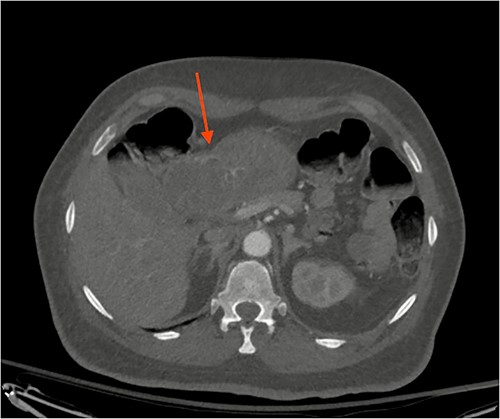

A 72-year-old patient with no past surgical history and a past medical history of developmental delay, hypertension and hyperlipidemia presented to the Emergency Department in mild distress with periumbilical abdominal pain, nausea and intractable vomiting for 1 day. The patient denied any hematemesis, bowel changes, fever, melena or hematochezia. On physical exam, the abdomen was unremarkable, and a computed tomography (CT) scan with contrast of abdomen and pelvis revealed a 5.6 × 5.3 cm heterogeneous mass arising from the body of the stomach extending into pylorus with no evidence of bowel obstruction and liver metastasis (Fig. 1). Subsequently, esophagogastroduodenoscopy (EGD) showed a large, fungating and ulcerated mass and it was reported to involve two-thirds of the luminal circumference in the gastric body (Fig. 2). Cold forceps biopsy showed gastric mucosa with hyperplastic changes, mild chronic active antral gastritis with focal intestinal metaplasia, negative for Helicobacter Pylori and dysplasia. Surgical management was discussed with the family, but they refused any surgical intervention.

CT scan image of abdomen showing heterogenous gastric mass (red arrow).